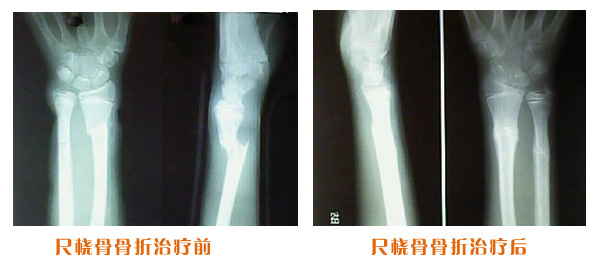

肥城市安駕莊梁氏骨科醫院是一所以梁氏手法正骨配合膏藥為特色的現代化專科醫院。

梁氏骨科術始創于清雍正年間,歷經八代,至今已有三百年歷史。據1929年泰安縣志載“梁瑞圖先生,字增生,號蓮峰,安駕莊人,精岐黃并發(fā)明接骨,凡跌打車凡跌打車軋皮不破而碎骨者......【詳細】 |